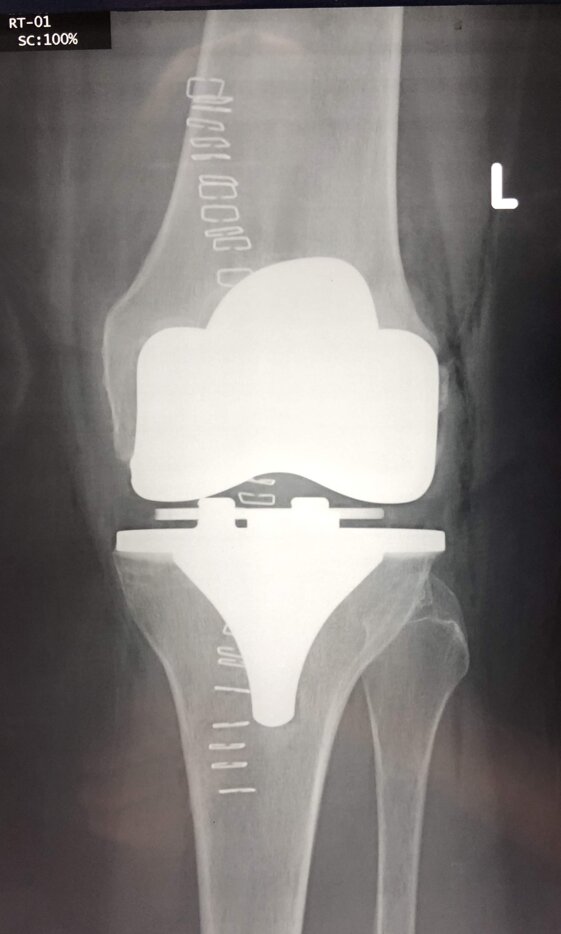

Radiografie post-operatorie in AP e LL di intervento chirurgico di artroprotesi cementata di ginocchio in pz donna con sovrappeso. In questo caso è stata utilizzata una protesi postero-stabilizzata (PS) con sacrificio quindi del legamento crociato posteriore (LCP)

Radiografie post-operatorie in AP di interventi chirurgici di artroprotesi cementate di ginocchio eseguiti in due pz con allergia ai metalli (nichel). Sono state utilizzate due protesi di due arche differenti, entrambe anallergiche (nichel-free) con conservazione del LCP (CR)